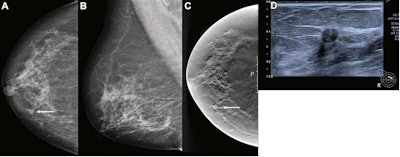

Artificial intelligence (AI) gave a score of 10 to this screen-detected ductal carcinoma in situ (DCIS) in a 68-year-old woman, indicating high risk for breast cancer. (A) Mammogram of right breast from the craniocaudal view. (B) Mammogram of right breast from the mediolateral oblique view. (C) Craniocaudal digital breast tomosynthesis (DBT) image of the right breast. (D) Ultrasound image of the right breast. The arrows in images A and C indicate the malignancy, with the dotted line in image D showing tumor diameter. Image courtesy of Radiology.A total of 957 breast cancers were included in the study, 752 being screen-detected and 205 being interval cancers. These came from 122,969 screening examinations taken between 2009 and 2018 from 47,877 women in Norway.